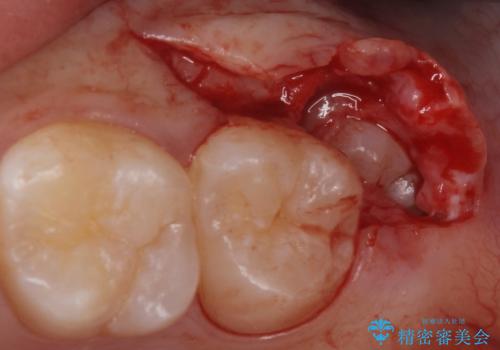

- 親知らずの抜歯希望で来院されました。

左側の親知らずを上下同時に抜いていきます。

時間は約60分で施術しました。

親知らずは入院せずとも通院で片側上下同時に抜くことが可能です。

手前の歯の虫歯リスクを下げるためにも、骨から出てきた親知らずは抜くことをお勧めします。